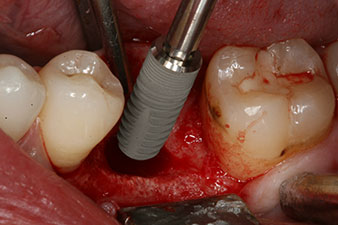

Figura 2: Seis semanas después, se observó un alvéolo que solo estaba osificado de forma incompleta en el área de la raíz mesial.

No obstante, seis semanas después de la extracción, tras la disección del colgajo mucoperióstico, se observó una osificación incompleta en el área del antiguo alvéolo mesial.

Implantat

Figura 3: Después de realizar la preparación con el motor de implantes Implantmed, se enroscó mecánicamente un implante (diámetro 4 mm, longitud 12 mm) con un torque de 43 Ncm.

Tras la extirpación minuciosa del tejido de granulación, se incorporó el implante tal como se había planificado (blueSky, bredent).